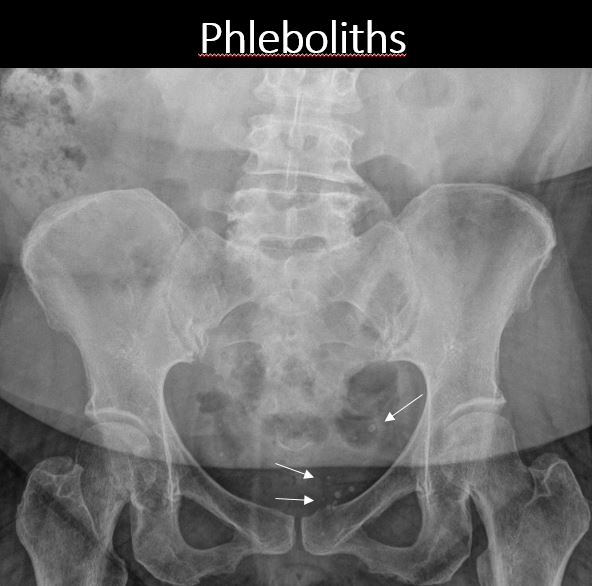

There are calcified phleboliths in the pelvis. [Yes/No]